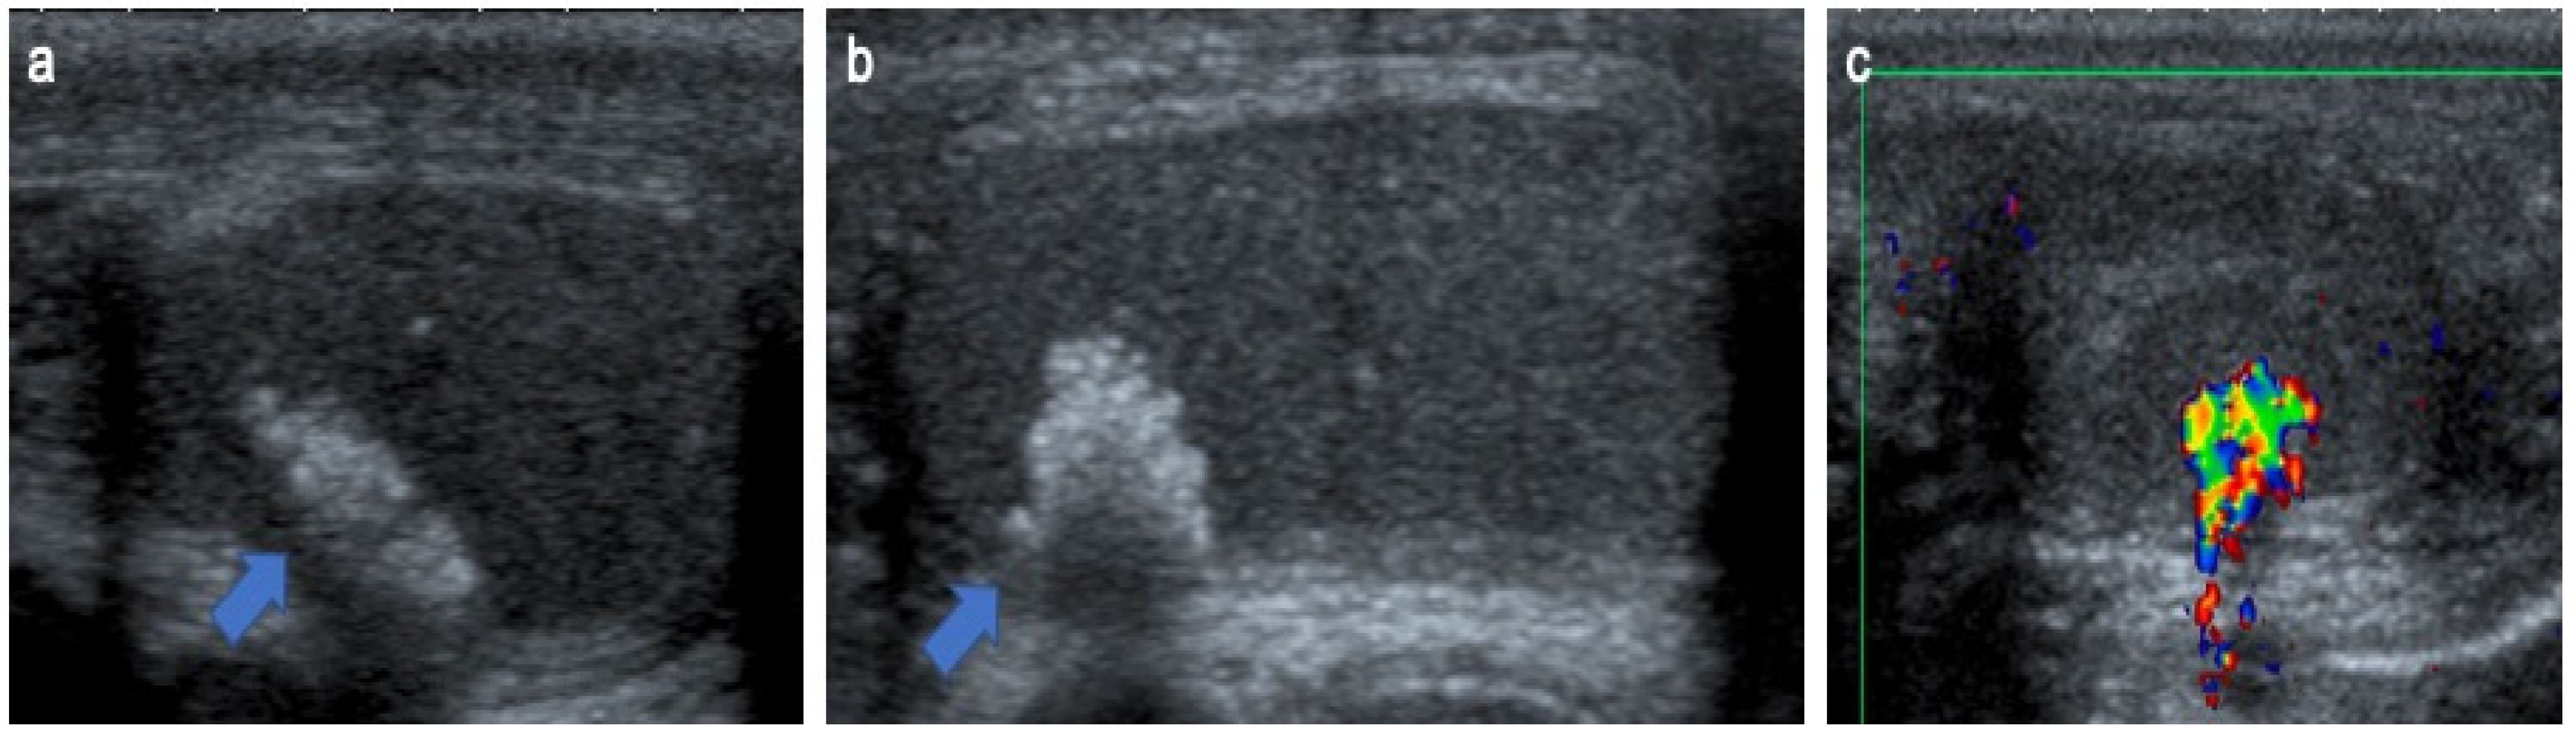

4.9. Testicular Adrenal Rest Tumors

- Yılmaz, R.; Şahin, D.; Aghayev, A.; Erol, O.B.; Poyrazoğlu, Ş.; Saka, N.; Yekeler, E. Sonography and Magnetic Resonance Imaging Characteristics of Testicular Adrenal Rest Tumors. Pol. J. Radiol. 2017, 82, 583–588. [Google Scholar] [CrossRef] [PubMed]

- Deshpande, S.S.; Shetty, D.; Saifi, S. Sonographic Appearance of Testicular Adrenal Rest Tumour in a Patient with Congenital Adrenal Hyperplasia. Pol. J. Radiol. 2017, 82, 526–529. [Google Scholar] [CrossRef] [PubMed]

- Mansoor, N.M.; Huang, D.Y.; Sidhu, P.S. Multiparametric ultrasound imaging characteristics of multiple testicular adrenal rest tumours in congenital adrenal hyperplasia. Ultrasound 2022, 30, 80–84. [Google Scholar] [CrossRef] [PubMed]